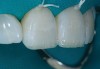

Then, the restorations for teeth Nos. 8 and 9 were created. Minimal augmentation would be required to improve the patient’s smile. The opaque shade was layered slightly irregularly to mimic the appearance of the patient’s natural dentition, particularly the interplay of the enamel and dentin optical properties (Figure 4). A putty matrix was inserted to guide composite placement when augmenting the shape and length of the central incisors using the CL composite (Figure 5). Then, a small amount of CL composite was applied as the final layer (Figure 6) and cured, after which a final polish was performed.

Fig 4. The opaque composite shade was layered slightly irregularly to mimic the optical properties of the patient’s natural dentition.

Figure 4